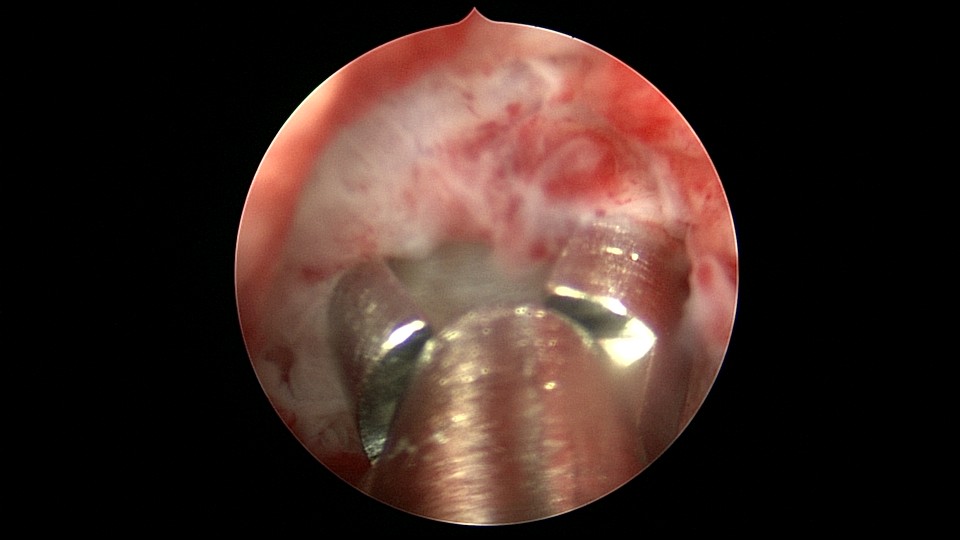

患者68岁,G3P1,顺产1次,安环42年,绝经20年,外院取环失败。子宫后位,宫颈及子宫萎缩,距宫颈内口1cm以上宫颈管封闭致密粘连,B超监护下异物钳分离粘连,打开进入宫腔的通道,艰难扩宫至6号扩宫棒,见O型环与两侧宫壁崁顿,异物钳无法取出,取环钩将环拉至宫颈外口,中弯钳牵拉,完整取出节育环,环变形,很艰难的取环经历。